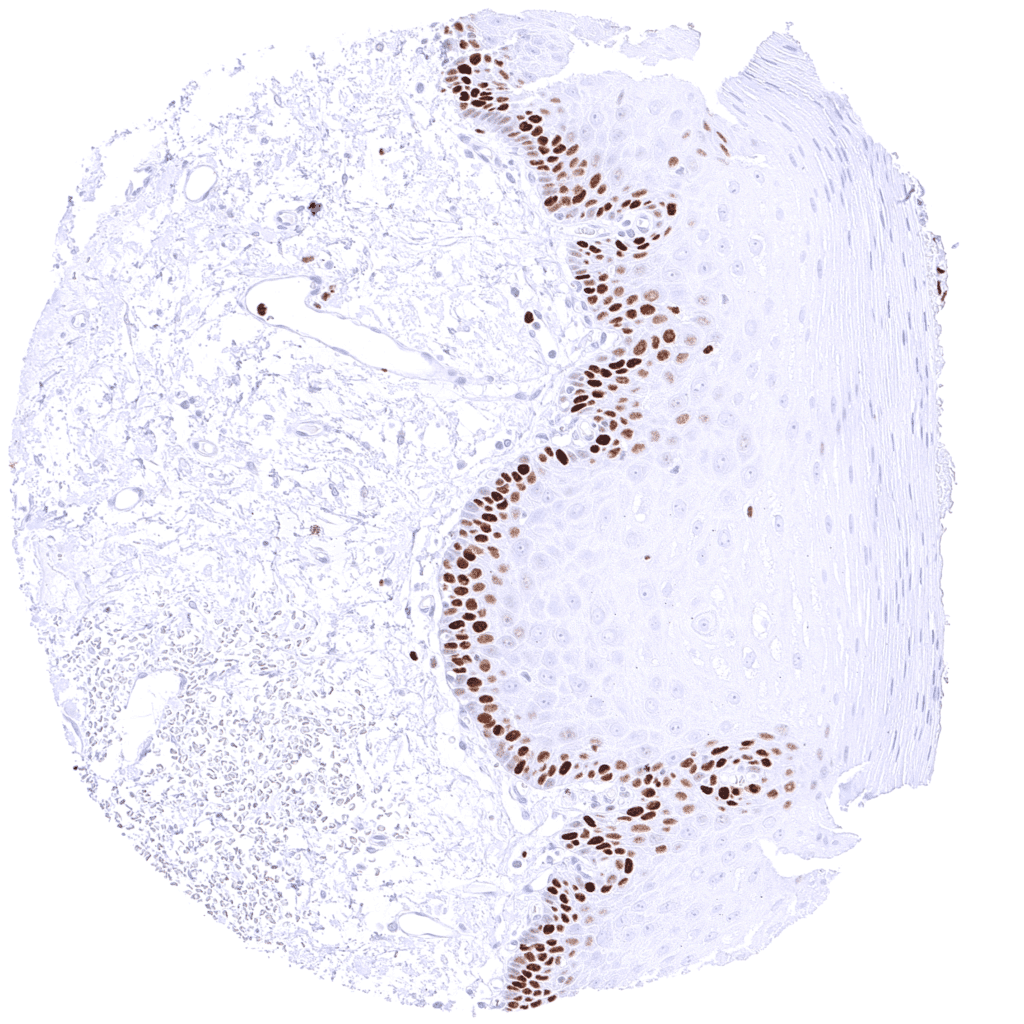

| Esophagus | Distinct MCM5 staining of suprabasal and (much less intense) basal cells of the squamous epithelium. | |

| Skin | Epidermis | Suprabasal and basal cells of the squamous epithelium show a distinct nuclear MCM5 positivity. |